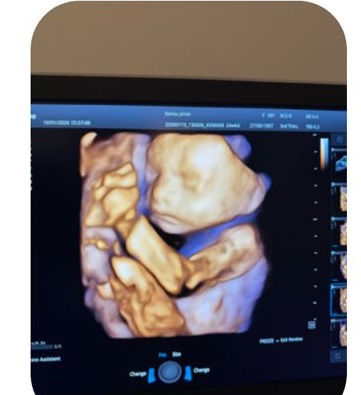

4 Boyutlu (4D) Ultrason Nedir?

4D ultrason, 3D görüntünün canlı ve hareketli hâlidir.

Bebeğin yüz mimikleri, el-kol hareketleri gerçek zamanlı izlenir.

Bazı yüz ve hareket anomalilerinin daha net görülmesi

📌 Günümüzde yapay zeka destekli 4D ultrason sistemleri, görüntü kalitesini ve ölçüm doğruluğunu daha da artırmıştır.